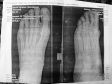

Два месяца назад обратилась в поликлинику с острой болью в стопе. В снимке отказали. Сказали, что артроз (ранее был установлен по снимкам). Прописали аркоксию. Черех 2-3 недели боль стала меньше. Но всё-равно боли периодически возникали. Спустя 2 месяца снова обратилась в поликлинику, настояла на снимке. Выявили: срастающийся субкапитальный перелом 2 плюсневой кости, избыточная периостальная костная мозоль, положение обломков с боковым смещением на толщину кортикального слоя. При этом сам момент травмы не помню, отеков, гематом не было. Наложили гипс. Отправляют на консультацию в другой город. Возможности самостоятельно добраться в гипсе нет. Каков прогноз на нормальное срастание кости? Как долго ходить в гипсе? Можно ли перемещаться (по квартире) без костылей, аккуратно ступая на пятку больной ноги?